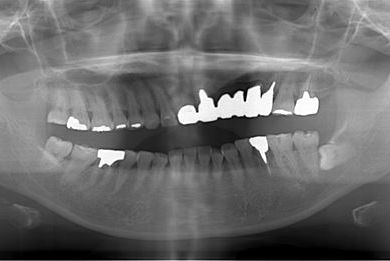

インプラントの症例写真 IMPLANT

| 主訴 | 以前治療した歯の歯ぐきから出膿。他の歯科でインプラントかブリッジしか方法がないが、骨の状態からインプラント治療は無理かもしれないと言われたことに不安を感じ、セカンドオピニオンを求めて来院。 | ||||||||||||||||||||||||||||||||

| 治療方針 | 保存不能の歯を抜歯し、インプラント治療にて機能的・審美的回復を行う。 | ||||||||||||||||||||||||||||||||

| 治療内容 | インプラント1本、ハイブリッドセラミッククラウン1本 | ||||||||||||||||||||||||||||||||